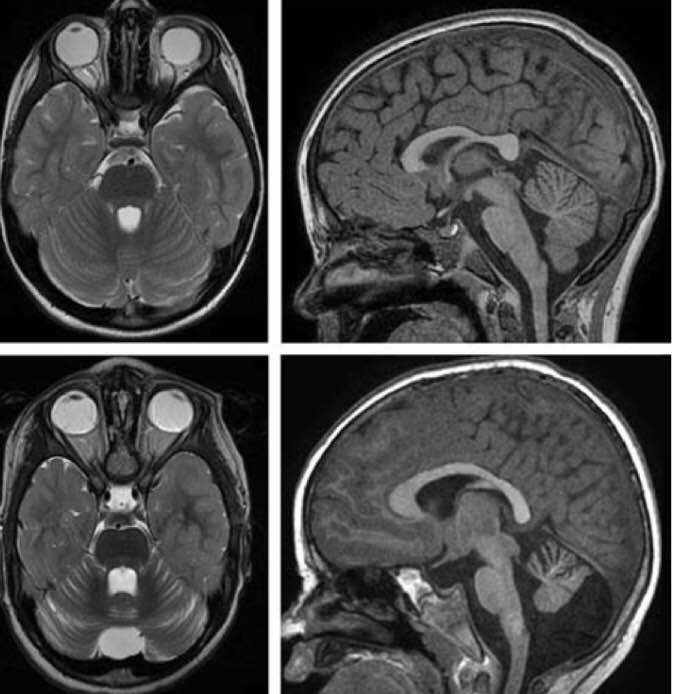

1. Agenesia

1. hipoplasia

1. Arnold Chiari

1. lesiones vasculares

1. Alteraciones metabolicas

1. Atrofias cerebelosas